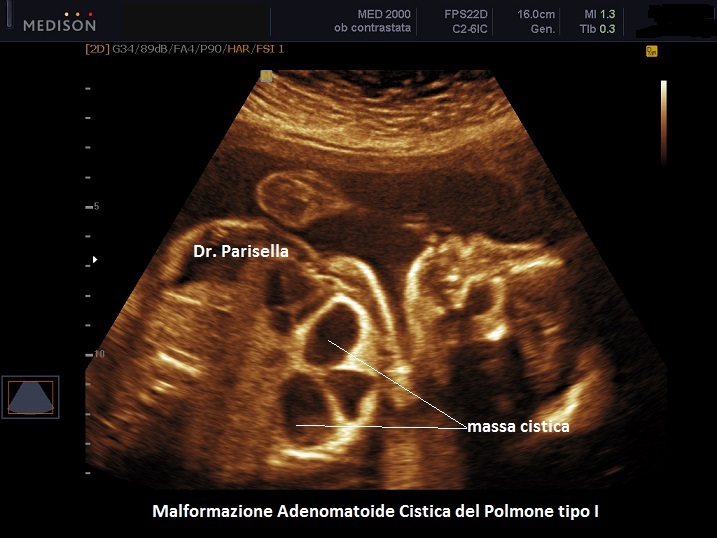

MACP tipo I: è caratterizzata da cisti singole o multiple di dimensioni solitamente > 2,0 cm;

. Il tipo I ha una buona prognosi, è presente in circa il 50% dei casi e le cisti sembrano comunicare con il normale parenchima polmonare e possono essere circondate da cisti più piccole.

Si presenta come una massa occupante spazio di solito unilaterale in più del 95% dei casi e solitamente coinvolge un lobo o segmento del polmone; nella sua evoluzione determina dislocazione del mediastino e del cuore. L'ecostruttura distingue due forme: una forma multicistica  caratterizzata dalla presenza di multiple cisti di varia grandezza (tipo I e II) e una forma microcistica (tipo III) corrispondente alla variante solida.